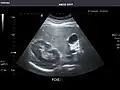

Renal ultrasonography

Ultrasonography of the kidneys is essential in the diagnosis and management of kidney-related diseases. The kidneys are easily examined, and most pathological changes in the kidneys are distinguishable with ultrasound.[7]

Kidneys: Right and left kidneys measure 11.5 cm and 12 cm in length respectively. No hydronephrosis. Small left lower pole kidney cyst.

Right kidney -

Left kidney -